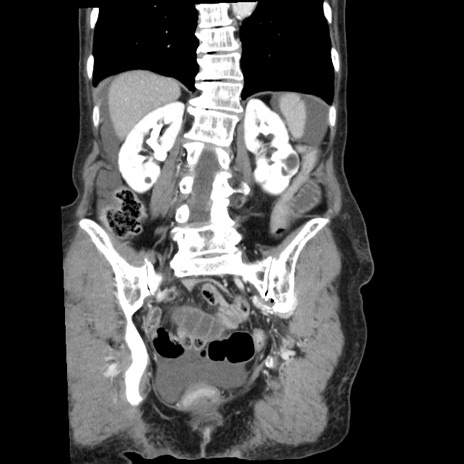

横断像

【症例】80歳代女性

【主訴】腹痛

【現病歴】8時間前から腹痛あり来院。

【既往歴】糖尿病、脂質異常症、子宮体癌にて子宮全摘術

【身体所見】意識清明・会話良好だが腹痛で苦悶様、全腹部にわたって反跳痛と圧痛あり

【データ】WBC 13600、CRP 0.14、LDH 224、CK 90